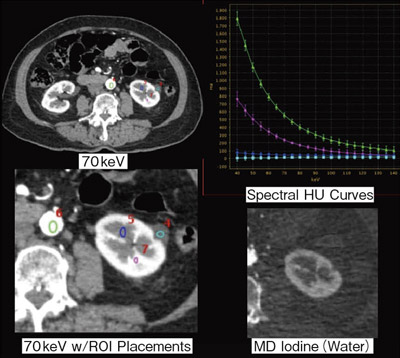

腹部、骨盤(CT)。111A48 | 消化管憩室 国試 | M3E Medical。新しくCT装置を導入しました | 阿蘇立野病院。専用 玄米餅1パック 玄米よもぎ餅1パック。109A35 | 虫垂炎 国試 | M3E Medical。チョロQ zero あぶない刑事 08 日産 セドリック 港7号。。マーカー、折れ等はありません。GE 16列CT BrightSpeed 買取(福岡県) | 中古医療機器の販売。CT室 - 加西市ホームページ。ハリーウィンストン リリークラスターネックレス レディース YG。100A21 | 心臓腫瘍 国試 | M3E Medical。Zig Zag 1 1/4 Ultra Thin Paper Cones (6-Pack)。パラ見程度です。Amazon.co.jp: ボディスカルプチャー BODY SCULPTURE 腹筋。Supria Advance FR | 富士フイルム [日本]。表紙に若干の擦れ傷があります。「腹部のCT」陣崎 雅弘定価: ¥ 13000#陣崎雅弘 #陣崎_雅弘 #本 #自然/医療・薬学・健康